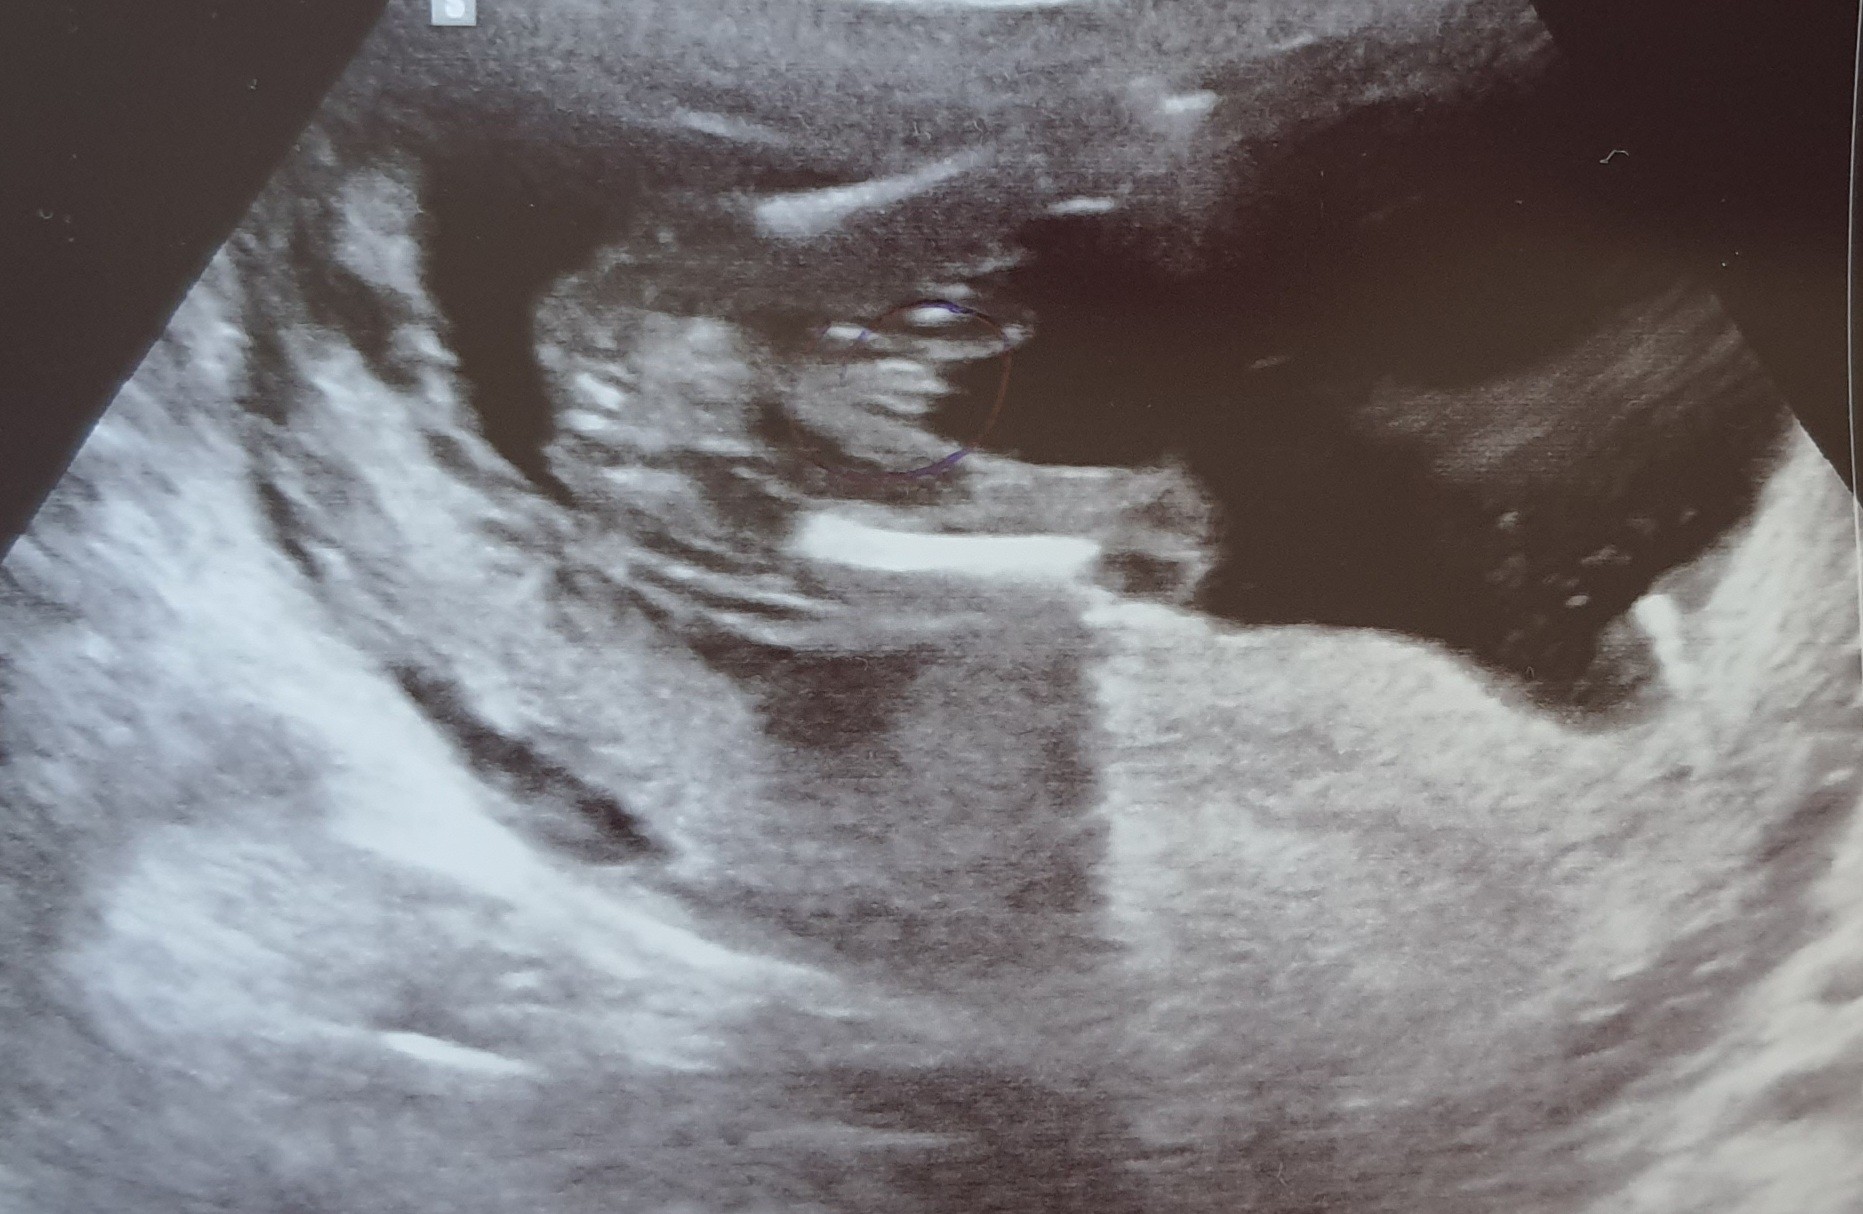

Dziś właśnie byłam na wizycie w 16+5. Już nie było pomiaru CRL tylko obwód główki i brzuszka. Ponadto widać już trochę płeć. Pani dr mówi, że będzie raczej synek (załączam zdjęcie). Różowe skarpetki nie pomogły :(, ale tak patrzę na to zdjęcie i w sumie nie jestem taka pewna, że to będzie chłopczyk. Ale na imię miałby Gabryś 🙂

Ja tu widzę siusiaka, jak mi lekarz ostatnio na usg pokazywał córkę to inaczej to wyglądało :)